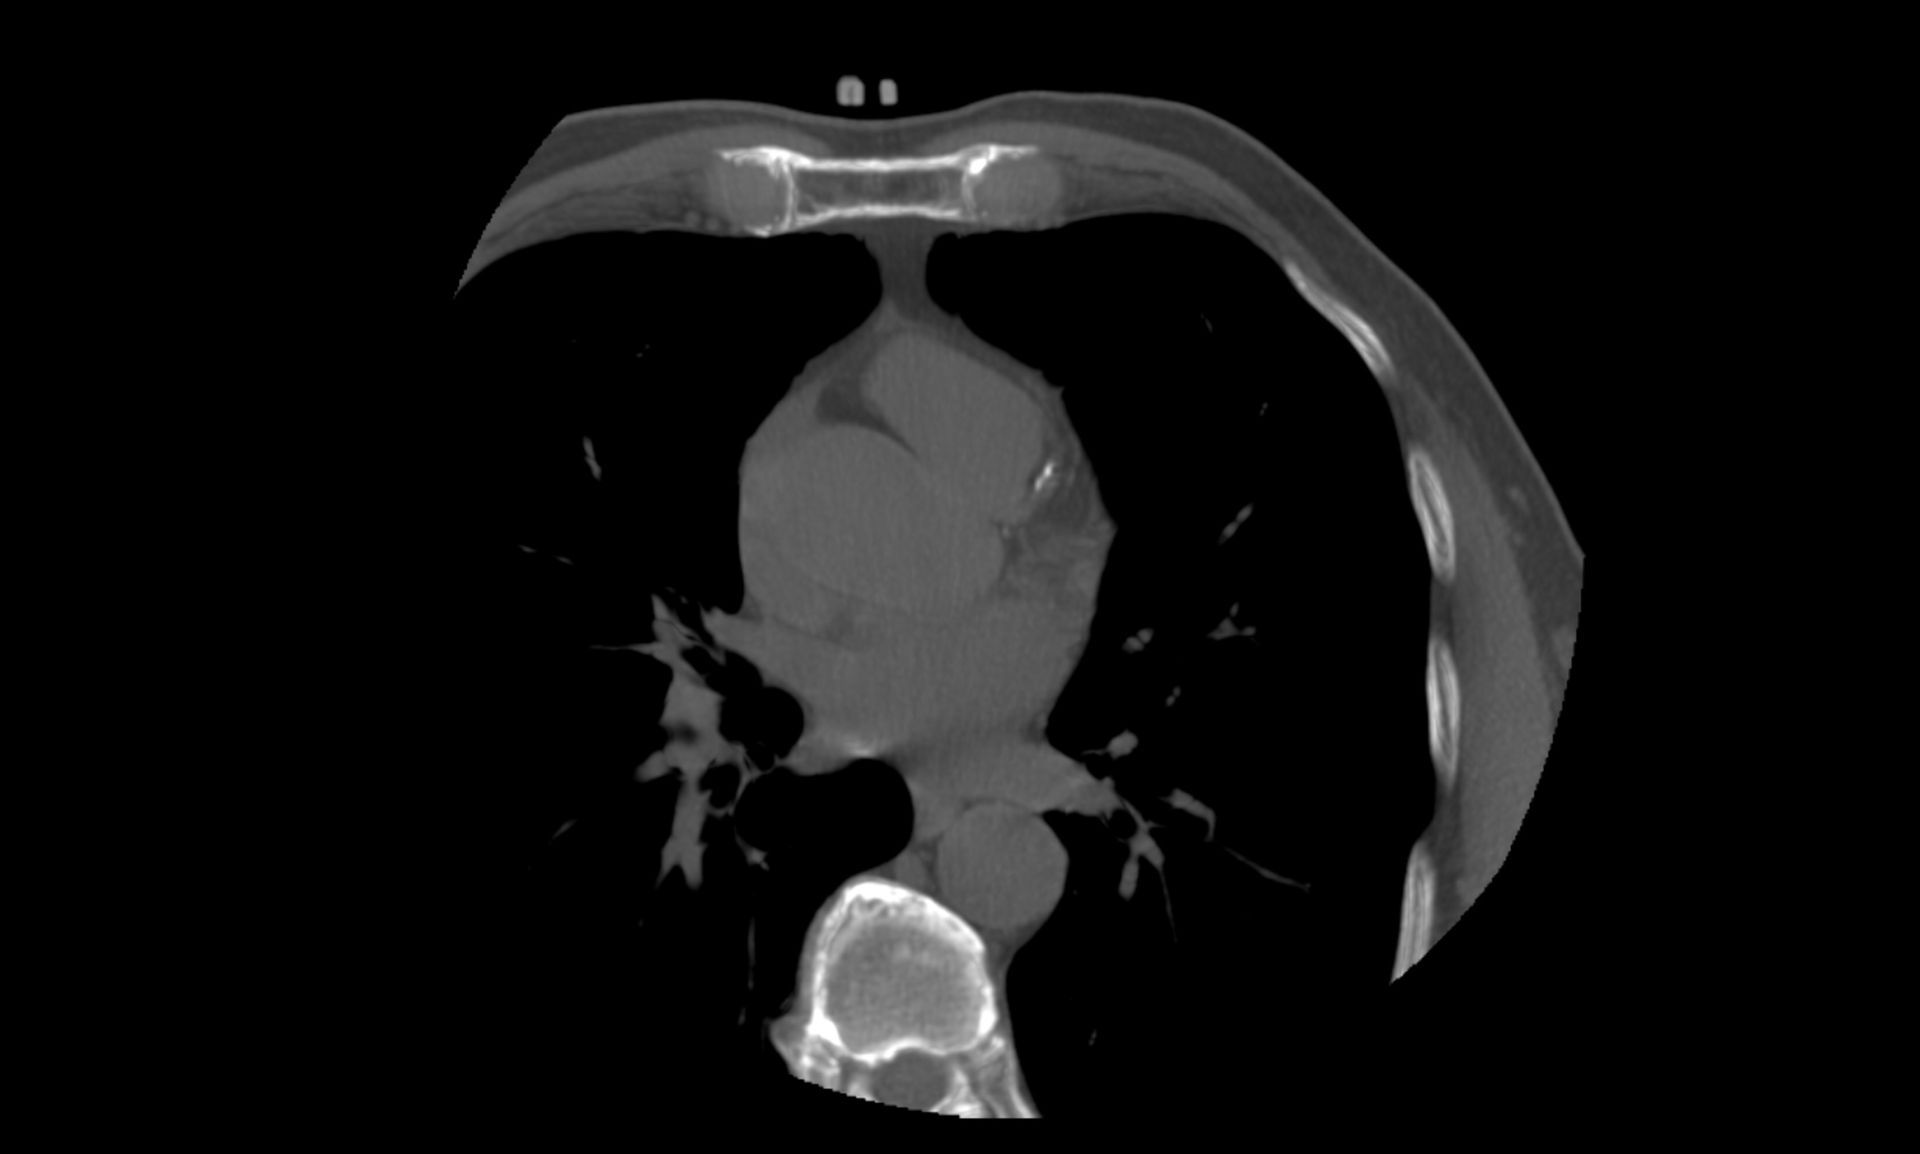

Cardiac calcium scoring tests can be used to determine the risk of cardiovascular disease and heart disease. The tests use a multi-slice CT scanner for the detection of small amounts of calcium or plaque in the coronary arteries. Images can show whether the coronary arteries are narrowed or blocked by any calcium or plaque build-up, which can be an indicator of heart disease.

The scanner takes a set of images before the table moves and more images are taken. State-of-the-art cardiovascular imaging software is then used to process the data and create cross-sectional images of the body that are displayed on a monitor. The procedure only takes a few seconds and can offer a detailed, multidimensional view.

Calcium scores have a high level of accuracy, due to the clarity of the results produced by the calcium procedure. The multi-slice CT scanner takes pictures of the heart in thin sections. When these images are combined, calcium deposits can be revealed, showing up as white specks. Imaging software can then calculate the score based on the calcification measured. An advantage of the CT cardiac calcium scoring test is that false positive or false negative calcium scores are very unlikely.